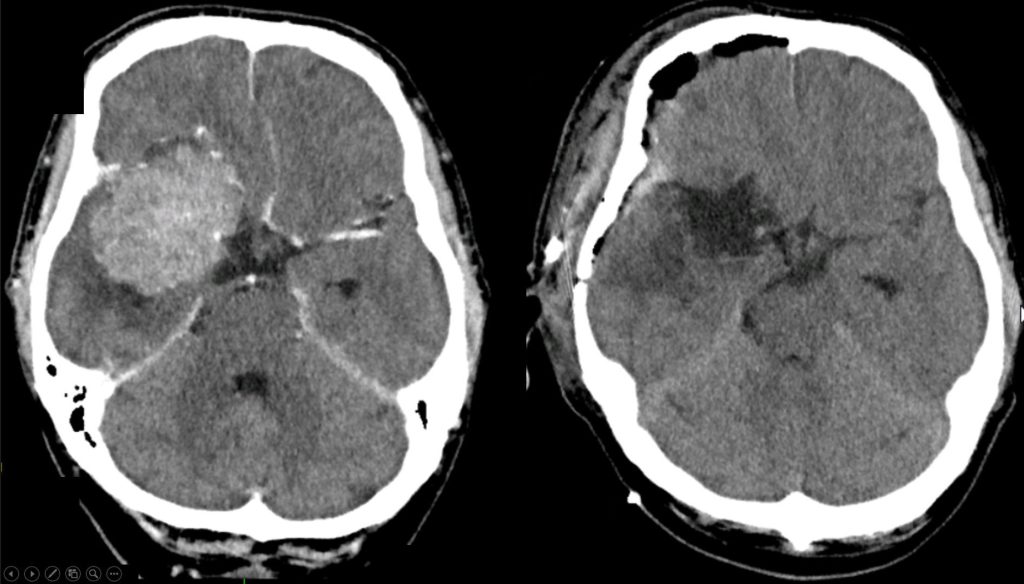

„V předchozích letech jsme ročně operovali kolem 40 pacientů s meningeomy. Meningeom je nezhoubný nádor vyrůstající z obalů mozku, který svým růstem tlačí na mozek a v konečném důsledku vede k úmrtí. Tento typ lze ve většině případů bezpečně a kompletně odstranit. V roce 2019 jsme těchto nádorů operovali 30. Teď během posledních dvou týdnů řešíme osm pacientů s tímto onemocněním. Operace tohoto typu nádoru jsou celodenní, náročné na čas i personál,“ vysvětluje zástupce primáře Neurochirurgického oddělení Jiří Fiedler.